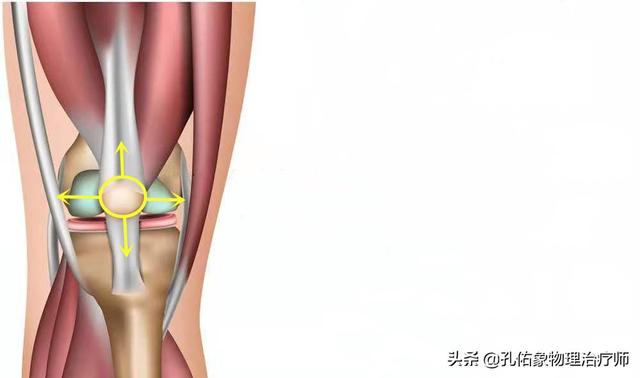

膝を伸ばすと、膝蓋骨は膝関節の屈曲と伸展に伴って動いていることがわかります。膝蓋骨の下には、いわゆる膝蓋下脂肪体があり、膝関節伸展の構造上重要な部分です。膝蓋下脂肪体は、膝関節伸展運動のクッション効果を持ち、膝関節伸展運動を円滑な構造に保つ働きがあります。

一般的に、このような構造は、膝関節を繰り返し使う中で摩耗や損傷を引き起こし、膝関節の動きに何らかの影響を与えることになり、動作時のガタつきはその表れのひとつと考えられる。